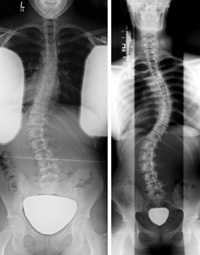

脊柱侧弯是指脊柱垂直方向的偏离。虽然有许多关于脊柱侧弯治疗方法的研究,但关于其病因和病理的研究数量有限。

本研究的目的是探讨不同类型的脊柱侧凸;其曲线与病因学理论;并注意它们对治疗的影响。我们使用“脊柱侧凸”、“病因学”、“病理学”、“保守治疗”等关键词对Pub MED、Medline、Cinhal、Cochrane library、谷歌scholar等电子数据库进行了检索。对获得的文章的参考文献也进行交叉参考。搜索范围仅限于英语文章。共145篇关于脊柱侧凸的患病率、病史、症状、分类、生物力学、发病机制、运动学和治疗的论文被鉴定为相关。要选择合适的脊柱侧弯矫正治疗方法,首先需要了解脊柱侧弯的病因和发病机制。

脊柱侧弯最常影响女孩。有些人的脊椎更容易弯曲。在生长高峰期,弯曲通常会变得更糟,往往呈字母S或C型。

必要时进行体格检查。你将被要求做弯腰实验。这使你的脊椎更容易看到。但在脊柱侧凸的早期可能很难看到变化,必须借助X光片等其他影像学检查。

以上问题可在学校或体检时进行儿童或青少年脊柱侧弯筛查与脊柱侧弯矫正。如果看起来有问题,医生会根据你的病史、家族史、体格检查和影像学检查来做出诊断。治疗取决于你的年龄,你可能长多高?有多少弯度?弯度是暂时的还是永久的?轻度脊柱侧弯患者可能会定期检查或接受保守治疗,看看曲线是否变差了。对于特别严重的缓和可能需要戴护具或做手术。